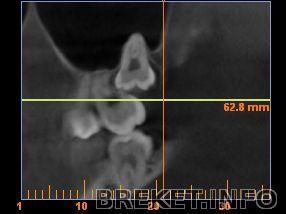

Трубочка под зубом - это мой нерв.

Наверно правильнее сказать что зуб не близко от нерва, а сидит в нём...

а это верхняя, нехило так упёрлась в корень семерки и все свои корни высунула в гайморову пазуху...